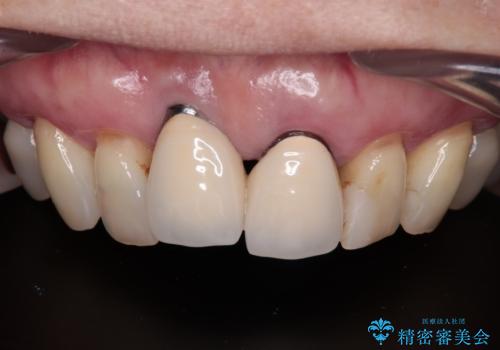

前歯のインプラントは埋入されたポジションが望ましい位置ではなく、インプラントを活用して段差を回収することは不可能と判断し、歯肉移植によりインプラントを隠して、ブリッジにて歯肉ラインを整えることとしました。

臼歯部の治療も必要と判断されましたが、前歯部を中心とした審美領域をオールセラミッククラウンによる補綴治療を行うこととしました。